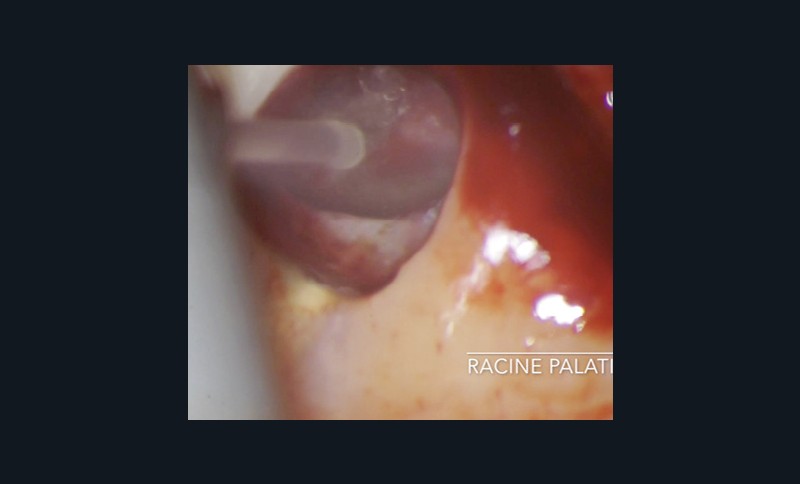

Chirurgie endodontique

L’Er:YAG a également sa place en chirurgie endodontique. En mode ablatif, il permettra l’élimination des tissus de granulation et des tissus fibro-kystiques en assurant la stérilisation de la crypte osseuse ainsi formée.

La résection apicale et la préparation a retro exposent des canaux et des tubulis dentinaires infectés, qui pourront là aussi, être décontaminés par l’action du laser Er:YAG et de l’eau distillée [36].

Les espaces non accessibles à l’instrumentation conventionnelle pourront, là aussi, être débridés et stérilisés (fig. 11a à f). Cette procédure semble accélérer de manière très significative les processus de régénération osseuse (fig. 11f).

Le laser Er:YAG permet de stériliser la partie apicale du canal, après l’avoir préparée a retro, ainsi que les tubulis dentinaires contaminés exposés.

Enfin, pendant la prise du matériau, le laser Er:YAG permet de pulvériser la lésion fibro-kystique et les tissus inflammatoires avant la réimplantation de la dent dans son alvéole ainsi stérilisée. Nous utilisons alors son mode photo ablatif décrit précédemment (fig. 12a à f).